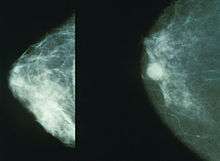

Implants and mammography

The presence of radiologically opaque breast implants (either saline or silicone) might interfere with the radiographic sensitivity of the mammograph, that is, the image might not show any tumor(s) present. In which case, anEklund view mammogram is required to ascertain either the presence or the absence of a cancerous tumor, wherein the breast implant is manually displaced against the chest wall and the breast is pulled forward, so that the mammograph can visualize a greater volume of the internal tissues; Nonetheless, approximately one-third of the breast tissue remains inadequately visualized, resulting in an increased incidence of mammograms with false-negative results.[86]

Silicone implant rupture can be evaluated using magnetic resonance imaging; from the long-term MRI data for single-lumen breast implants, the European literature about second generation silicone-gel breast implants (1970s design), reported silent device-rupture rates of 8–15 per cent at 10-years post-implantation (15–30% of the patients).[56][57][58][59]

The study Safety and Effectiveness of Mentor’s MemoryGel Implants at 6 Years (2009), which was a branch study of the U.S. FDA’s core clinical trials for primary breast augmentation surgery patients, reported low device-rupture rates of 1.1 per cent at 6-years post-implantation.[60] The first series of MRI evaluations of the silicone breast implants with thick filler-gel reported a device-rupture rate of 1.0 per cent, or less, at the median 6-year device-age.[61] Statistically, the manual examination (palpation) of the woman is inadequate for accurately evaluating if a breast implant has ruptured. The study, The Diagnosis of Silicone Breast implant Rupture: Clinical Findings Compared with Findings at Magnetic Resonance Imaging (2005), reported that, in asymptomatic patients, only 30 per cent of the ruptured breast implants are accurately palpated and detected by an experienced plastic surgeon, whereas MRI examinations accurately detected 86 per cent of breast implant ruptures.[62] Therefore, the U.S. FDA recommended scheduled MRI examinations, as silent-rupture screenings, beginning at the 3-year-mark post-implantation, and then every two years, thereafter.[46] Nonetheless, beyond the U.S., the medical establishments of other nations have not endorsed routine MRI screening, and, in its stead, proposed that such a radiologic examination be reserved for two purposes: (i) for the woman with a suspected breast implant rupture; and (ii) for the confirmation of mammographic and ultrasonic studies that indicate the presence of a ruptured breast implant.[63]